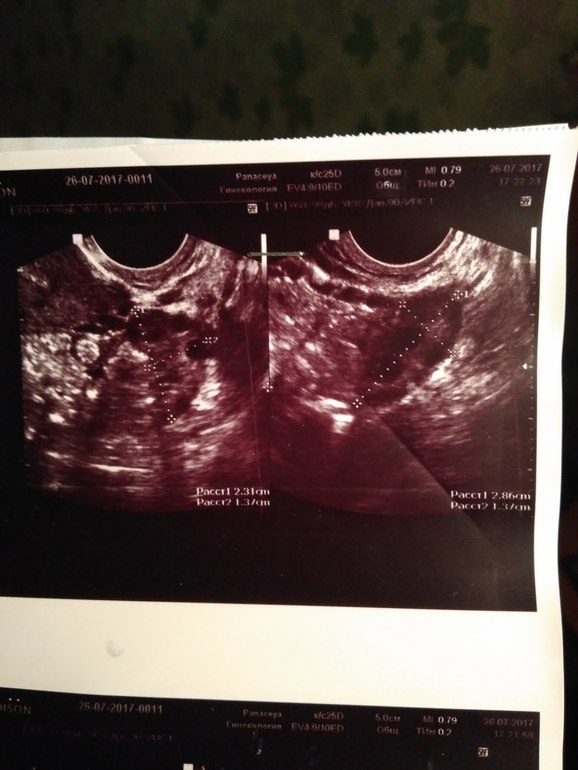

похоже на мфя или спкя? Если вы знаете конечно как выглядит на УЗИ это. Это на 5дц

Нашла УЗИ с конца июля, сразу после М, в августе делала ещё, результат у Г к сожалению.